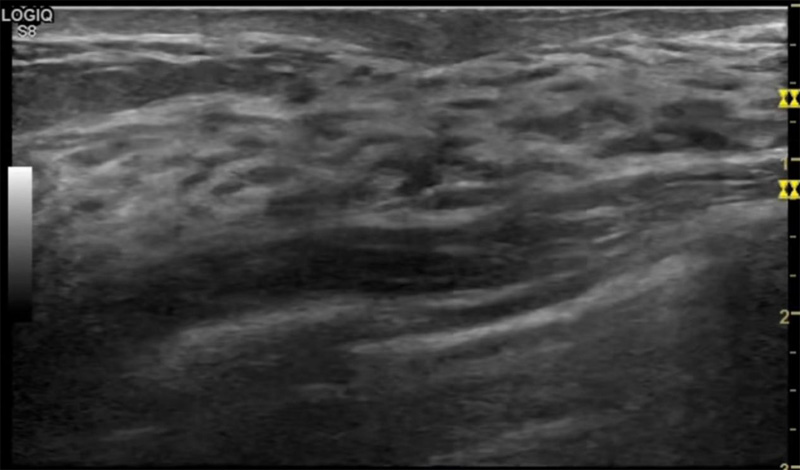

乳房脹痛,觸摸疼痛,手摸起來感覺有腫塊。這個是什么問題呢?醫(yī)生診斷一般是乳腺增生。那么在乳腺超聲設(shè)備檢查后,報告單卻顯示雙乳未見明顯占位性病變。乳腺增生是很多女性,特別是育齡期女性都有的經(jīng)歷、到底乳腺增生癥狀有哪些?會給我們帶來怎樣的影響呢?乳腺增生不是腫瘤跟炎癥。乳腺組織增生及退行性變跟內(nèi)分泌功能紊亂有關(guān)系。正常的生理改變。還有乳腺病,良性乳腺結(jié)構(gòu)不良等名稱。

乳腺增生有什么癥狀,病因?比較典型的就是乳房疼痛,特別是經(jīng)前癥狀比較重,經(jīng)后就有所緩解。有時候還能碰到乳房硬塊。根據(jù)經(jīng)期的變化而變化硬度大小都有變。乳腺在內(nèi)分泌激素,伴隨月經(jīng)周期有增生問題。內(nèi)分泌激素代謝失衡,雌激素水平增高,出現(xiàn)乳腺組織增生過度,增生組織不退的情況下,就會有乳腺增生癥狀。這個不會增加乳腺癌的風(fēng)險。所以不用緊張的。不過乳腺癌的病人都會有乳腺增生。所以乳腺增長有沒癥狀,都需要進行常規(guī)的體檢。